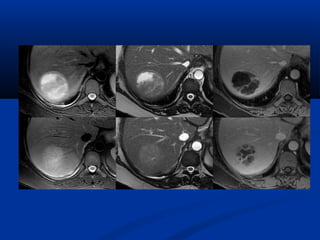

Choline vaø lactic acidPHOÅ COÄNG HÖÔÛNG

TÖØ

(SPECTROSCOPY/MRS)